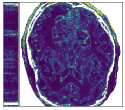

Figure 5 shows an example of a spatio-temporal regularization parameter-map which was estimated using the proposed approach for an acceleration factor of . The network estimates the regularization parameter-map to be pointwise relatively consistenly higher than the spatially required regularization. This result is in fact expected as the temporal dimension is the one for which the gradients of the images are the sparsest because of the high temporal correlation. Further, we see how the network consistently predicts both the spatial regularization as well as the temporal regularization to be less strong in the area where most of the movement is expected, i.e. in the cardiac region.

Figure 6 shows examples of the quantitative (magnitude) images of three of the 112 simulated inversion recovery measurements in the test dataset. We also show the regularization parameter-maps for regularization along the spatial directions and along the inversion-time direction generated by the network. The mean PSNR and SSIM of our proposed method is consistently higher for all considered acceleration factors, even compared to PDHG with regularization strength along spatial and inversion-time direction chosen by grid-search with access to the ground truth images (shown in Figure 8 and Table 2). The resulting parameter-maps after performing the regression on the reconstructed images are shown in Figure 7. Again, our proposed method results in the lowest RMS deviation from the ground truth images (Table 2).